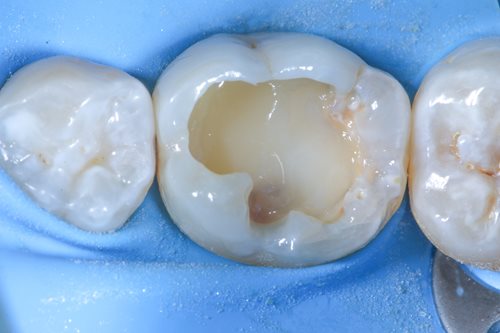

Dr. Benjamin used Komet BioRepair putty material to cover the treatment area and seal the cavity. To create an optimal bonding effect, he applied a self-adhesive flow to the BioRepair material and sandblasted the whole area.

After selective etching and the composite shaping took place with hand instruments and a small brush. He used tooth colours to create realistic depth of colour and let the filling look like a natural, healthy tooth surface. As a last step, he polished the whole treatment area and performed a bite test. The positive result marked the end of a completely successful treatment.

Having completed the endodontic treatment successfully, Dr. Benjamin was able to preserve his patient’s tooth and prevent tooth loss. Thanks to the BioRepair putty material, the vitality of his patient’s tooth could be preserved, and the application of tooth colours ensured an aesthetically pleasing result.